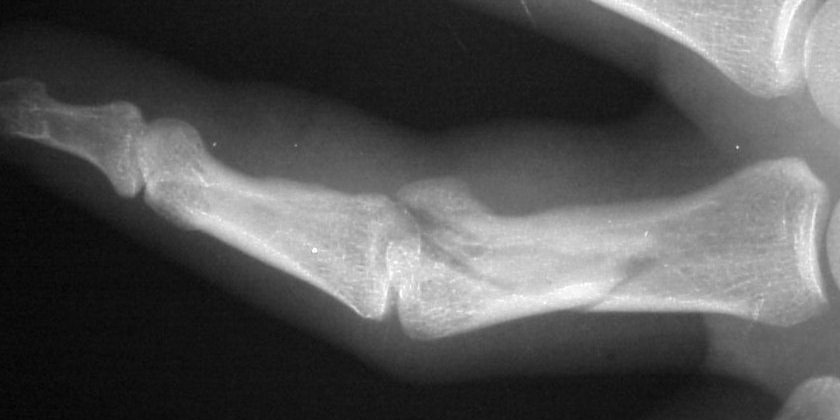

Clinical Example: Proximal phalanx bicondylar oblique volar coronal head fracture

This gentleman sustained a closed severe torsional injury of the right ring finger.

Xrays show a complex intraarticular fracture of the proximal phalanx head. There is a displaced spiral oblique longitudinal fracture with a second oblique coronal split through the articular surface of the radial condyle.